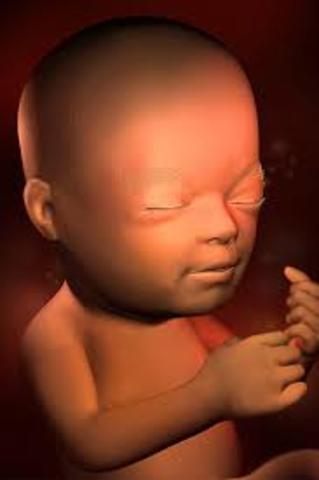

• Week 27

Welcome to the last trimester! The fetus is now 14.5 inches long and 2 pounds. The hearing is developing more and more and the eyes are active now.

• Week 28

Week 28

The fetus is now coming to a close 14.8 inches and 2.2 pounds! The milk teeth are in the gums now and the scalp hair is now defined.